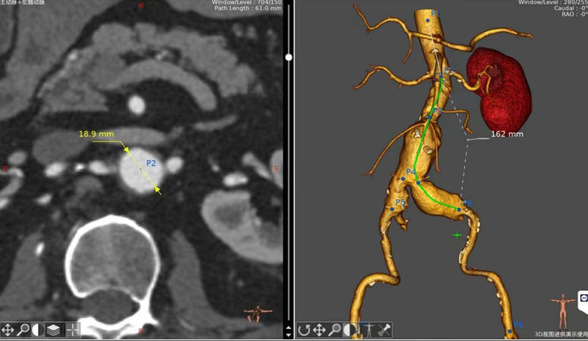

近日,我院血管外科成功“拆除”2025年第一枚“炸弹”。患者唐大爷由于尿潴留来我院泌尿外科就诊,然而这枚埋藏在腹部多年的“不定时炸弹”成了解决排尿不畅的最大阻碍。血管外科李喜春主任团队应邀会诊,向患者及家属详细分析病情,患者于次日转入血管外科完善相关检查。由于病情相对复杂,病变累及双侧髂动脉,经过对动脉CTA各部位精确测量制定手术方案,心内科、胸心外科、呼吸与危重症医学科和麻醉科等各位专家进行多学科会诊评估手术风险,3日后通过杂交手术的形式历时两小时完成手术,患者于术后第二日返回病房,各项生命体征平稳。

术中影像